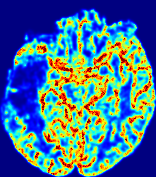

LesionRefer to captionRefer to captionRefer to captionRefer to captionRefer to captionRefer to caption𝐕rgbsubscript𝐕𝑟𝑔𝑏{\bf{V}}_{rgb}Refer to captionRefer to captionRefer to captionRefer to captionRefer to captionRefer to caption𝐕2subscriptnorm𝐕2{\|\bf{V}}\|_{2}Refer to captionRefer to captionRefer to captionRefer to captionRefer to captionRefer to captionRefer to caption3.53.53.52.82.82.82.12.12.11.41.41.40.70.70.70.00.00.0(mm/s)𝑚𝑚𝑠(mm/s)D𝐷DRefer to captionRefer to captionRefer to captionRefer to captionRefer to captionRefer to captionRefer to caption0.0200.0200.0200.0160.0160.0160.0120.0120.0120.0080.0080.0080.0040.0040.0040.0000.0000.000(mm2/s)𝑚superscript𝑚2𝑠(mm^{2}/s)Slice #1Slice #2Slice #3Slice #4Slice #5Slice #6

Figure 4: PIANO feature maps for another patient in the ISLES 2017 training set, where the lesion is located in the right hemisphere. Top row: segmented stroke lesion region (white) on different slices. The corresponding slices for the PIANO feature maps are shown in the following rows.

For a better insight into an estimated velocity field 𝐕𝐕{\bf{V}} and diffusion field 𝐃𝐃{\bf{D}}, we compute the following maps: (1) 𝐕rgbsubscript𝐕𝑟𝑔𝑏{\bf{V}}_{rgb}: Color-coded orientation map of 𝐕=(Vx,Vy,Vz)T𝐕superscriptsuperscript𝑉𝑥superscript𝑉𝑦superscript𝑉𝑧𝑇{\bf{V}}=(V^{x},V^{y},V^{z})^{T}, obtained by normalizing 𝐕𝐕{\bf{V}} to unit length and mapping its 3 components to red, green, blue respectively; (2) 𝐕2subscriptnorm𝐕2\|{\bf{V}}\|_{2}: 222 norm of 𝐕𝐕{\bf{V}}; (3) D𝐷D: scalar field in Eq. 5.

Fig. 3 and Fig. 4 show the PIANO feature maps estimated from two ISLES 2017 patients: all are highly consistent with the lesion in both cases. Details of the blood flow trajectories are revealed in 𝐕rgbsubscript𝐕𝑟𝑔𝑏{\bf{V}}_{rgb} by the ridged patterns and the sharp changes of colors in the unaffected (right) hemisphere, while the flat patterns appearing within the lesion provide little directional information about the velocity and indicate low velocity magnitudes. Velocity magnitudes are more directly visualized via 𝐕2subscriptnorm𝐕2\|{\bf{V}}\|_{2}, from which one can easily locate the lesion where 𝐕2subscriptnorm𝐕2\|{\bf{V}}\|_{2} is low. D𝐷D also indicates lower diffusion values in the lesion, though with less contrast potentially due to the fact that it captures the accumulated effect of CA diffusion at the voxel-level.